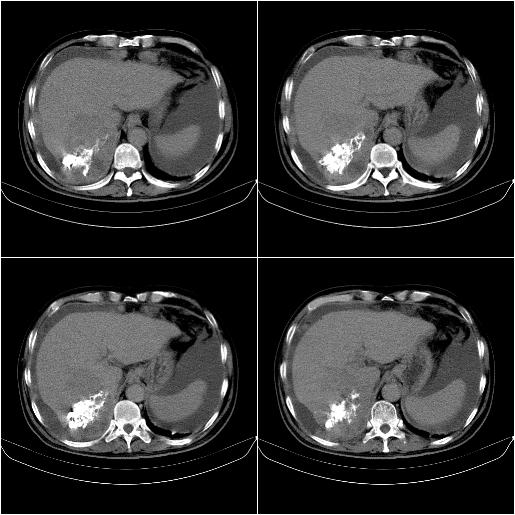

标题: CT21651:M,67Y,肝癌9月,介入术后3月。

m,67y,肝癌9月,介入术后3月。现腹胀、纳差、腹泻。

门静脉有很大的瘤栓,膈肌及膜膜有转移,不用再做了.

1)肝癌介入治疗术后碘油沉积不良。2)门静脉瘤栓形成,腹膜广泛性转移。3)肝硬化,脾大,腹水。4)慢性胆囊炎。